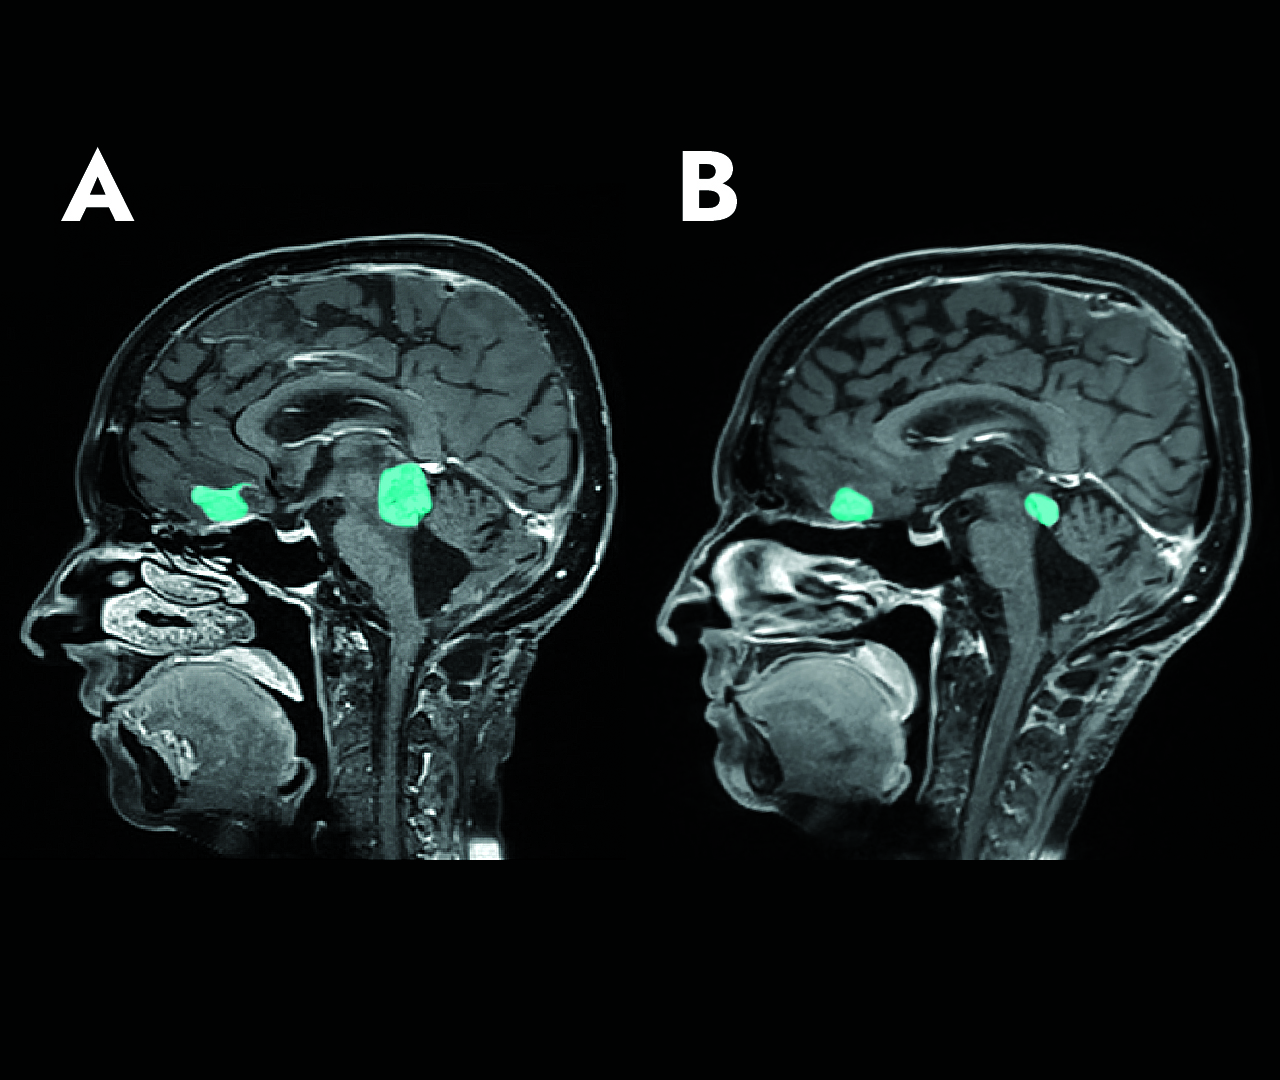

A first in autism: artificial intelligence helps identify children for whom bumetanide could be considered as a treatment

While there is still no approved drug treatment to reduce the main symptoms of autism, a study published in the journal...